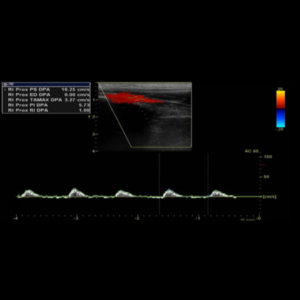

Ecografía Doppler Arterial

La ecografía Doppler arterial es un estudio de ecografías que estudia las diferentes ramas arterias de miembro superior o inferior, evaluando su calibre y descartando la presencia de placas ateromatosas o estrechez que indiquen un flujo lento, por lo tanto descarta insuficiencia arterial.